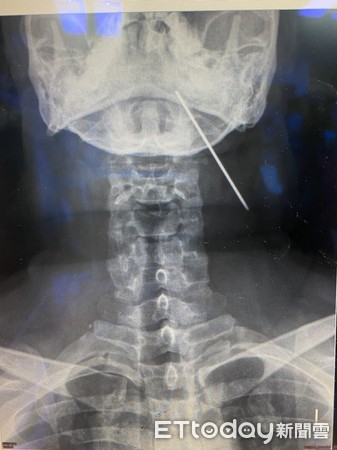

▲2015年X光片,鋼釘橫躺在頸部。(圖/記者許宥孺攝)

經調閱男子過去病歷,發現男子體內的鋼釘在2015年時早就移位,本來應該在右肩,卻

橫躺在頸部,畫面相當嚇人,2016年則是移到左邊鎖骨,2017年再度回診,這根鋼釘卻

是硬生生的向上直插顱底處,讓李家和直呼相當驚險:「這就像射標槍一樣!」

▲2017年X光片,鋼釘插在左顱底。(圖/記者許宥孺攝)